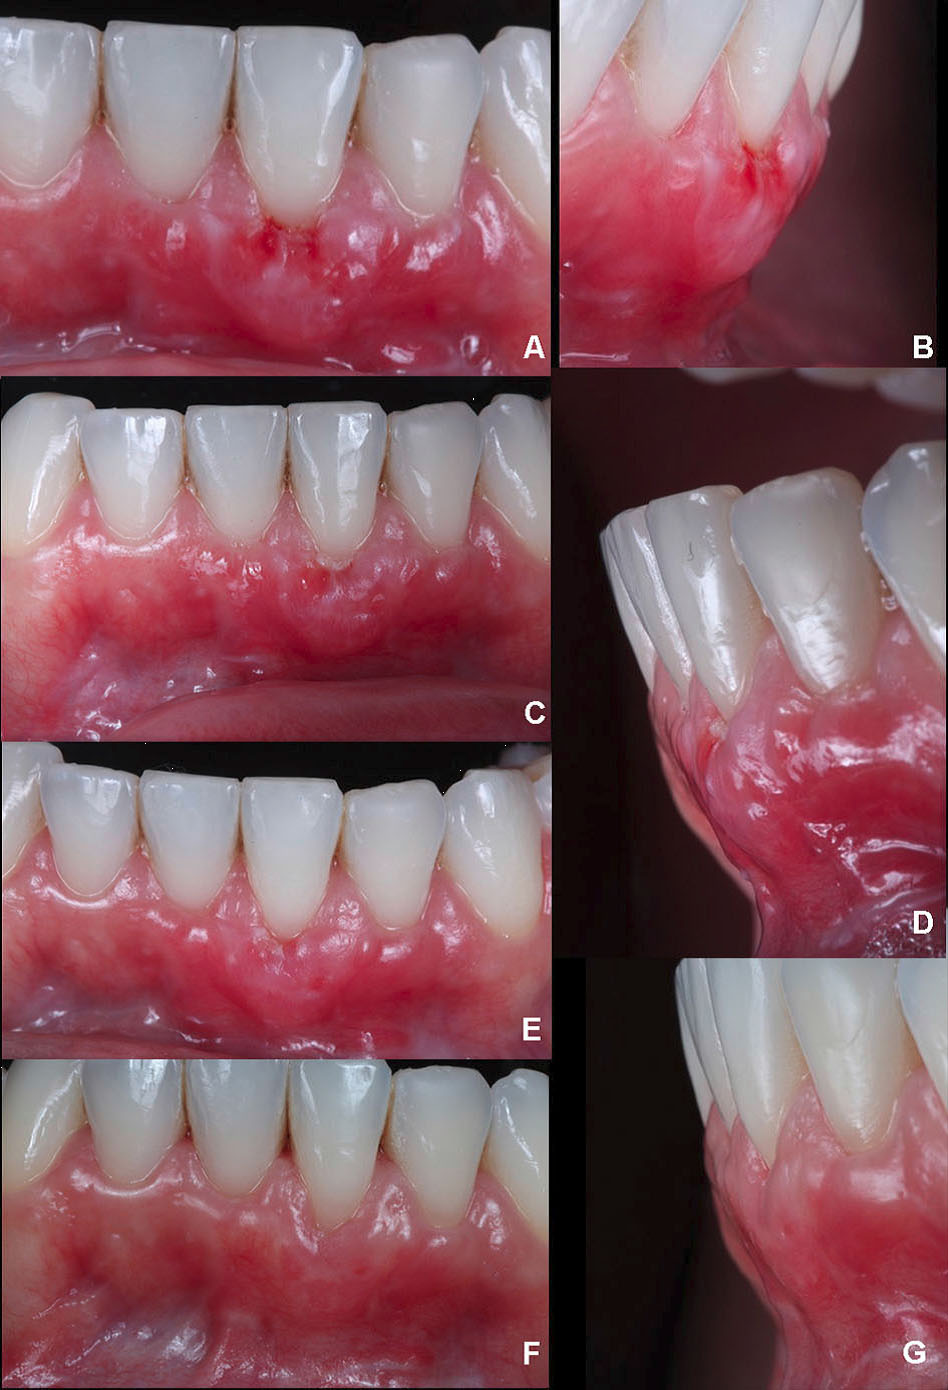

The patient was closely monitored to detail the postoperative period. Thereby, after two days, it was possible to observe a small white layer from the SCTG in the gingival margin (Figure 4A). In 4 days, there was a better tissue integration with a slight modification of the color on the white zone initially found (Figure 4B). After six days, when the sutures were removed, an interesting initial outcome was achieved, with stable tissue healing with no graft and volume loss (Figure 4C, D).

Figure 4.

A. After two days, the initial healing with a white layer of the SCTG. B. After four days, a decrease in the white zone was evident, suggesting initial vascularization and adaptation of all tissues. C. Six days after the sutures were removed; the early healing phase. D. Lateral picture at six days, showing that the volume was preserved. E. Nine days after surgery, the frontal image shows the remodeled tissue. F. Lateral picture at nine days showing that the volume was gained.

Within nine days, a high level of vascularization and integration of the soft tissue graft was verified, reducing the white layer and maintaining the volume. Nevertheless, there was a reduction of tissue height in the facial zone (Figure 4E, F) compared to the outcome at six days. After 11 (Figure 5A, B) and 13 days (Figure 5C, D), improved healing was found with slight differences between them. In 16 days (Figure 5E), it was possible to report stable tissues, confirmed after 31 days (Figure 5F, G), with a significant GR reduction and increased KTW and GT. Moreover, it improved the PES analysis score from 5 (day 0) to 9 (31 days).